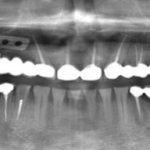

Строение зубного имплантата в картинках

Готовясь к имплантологическому лечению, пациент узнает много новых слов и терминов, в которых порой